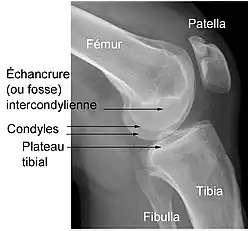

- l’extrémité supérieure du tibia, encore appelé plateau tibial ;

Une blessure du LCA arrive typiquement à la suite d'un changement de direction. Souvent, on a affaire à une rotation de la jambe vers l'extérieur, le corps se tournant vers l'intérieur, ou inversement. Le déclencheur peut également être un mouvement d'extension ou de flexion exagéré (respectivement hyperextension ou hyperflexion). Elle arrive également souvent pendant la réception d'un saut lourdement ou sur une jambe tendue, surtout quand l'atterrissage se fait sur les talons, le genou en rotation interne (pied en dedans). Ceci provoque un choc direct sur le tibia, alors que le condyle latéral du fémur est situé sur la partie inclinée vers l'arrière du plateau tibial. Ceci entraîne une force de glissement vers l'avant du tibia, essentiellement encaissée par le LCA.

Les facteurs anatomiques sont soupçonnés déjà depuis longtemps. La résistance à la rupture d'un LC dépend directement de sa largeur, qui varie d'un individu à l'autre. Dans une étude anthropométrique, les LCA du genou controlatéral intact de patients victimes d'une rupture de LCA ont été comparés avec ceux d'individus de même poids corporel. Les volumes des LC ont été déterminés par IRM. Dans le groupe des blessés, le volume des LCA contralatéraux était en moyenne 1 921 mm3, tandis que dans le groupe de contrôle, il était de 2 151 mm3. Les auteurs de l'étude en concluent que les différences anthropométriques des volumes – et de la largeur qu'on en déduit – des LC ont une influence directe sur la probabilité d'une rupture de LC sans agression externe[49]. Déjà dans des études précédentes, on a établi une corrélation entre cavité ligamentaire du fémur (notch intercondylaire : voir figure) étroite, liée à des ligaments plus étroits, et un risque plus élevé de rupture de LC[50],[51],[52],[53],[54],[55]. Cependant on n'est pas arrivé à un consensus scientifique, parce que d'autres études aboutissent à des résultats opposés[43],[56],[57]. Par rapport aux hommes, les femmes ont une cavité ligamentaire plus étroite, ce qui pourrait expliquer une incidence plus élevée des ruptures de LC chez les femmes[58],[59].